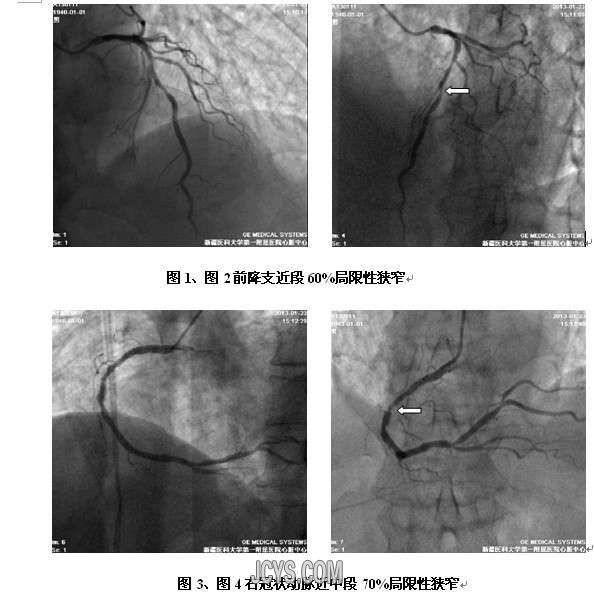

• 介入治疗的认识 attach_img agree

• 昨天参加郑州大学第一附属医院韩新巍教授做的【介入治疗的临床应用和研究进展】学术报告,虽然以往也看到这方面的知识,但是很是肤浅和局限,更重要是没有把它用于日常的医疗实践过程当中。可能很多基层医生 ...  阅读全文>